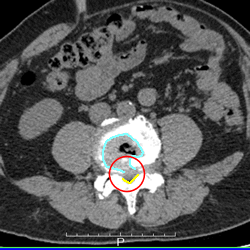

腰の骨ヘルニアのCT画像 CT画像

病院の救急

CTを撮ってもらい、尿管結石は見つからず、血尿もありませんでした。

レントゲン所見で、腰椎ヘルニアだと言われ、

ああ、そうかも、ヘルニアの部位と痛い足の部位も一致するな。

痛み止めの静注を打ってもらい、やや痛みが軽くなりましたが、立つことができず、車いすで駐車場に行き帰宅しました。